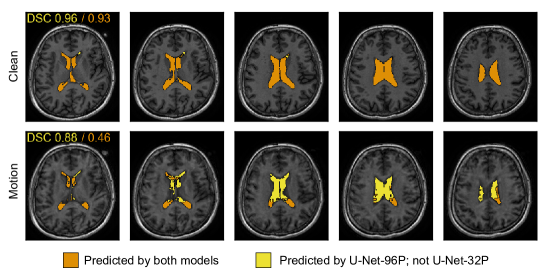

Refer to caption

Figure 8: Mild motion artifacts cause U-Nets trained with small patch sizes to miss segmentation predictions on large structures such as the lateral ventricles. Axial slices are shown 4 mm apart on the clean (no motion; top row) and motion-transformed (bottom row) T1 images of the same subject. DSCDSC\mathrm{DSC} values are shown in the top-left corner of each row for a U-Net trained on 96×96×9696969696\times 96\times 96 mm3 patches (U-Net-96P; yellow) and a U-Net trained on 32×32×3232323232\times 32\times 32 mm3 patches (U-Net-32P; orange).

Besides highlighting the sensitivity of modern DNNs to transformed/corrupted data in neuroimaging, one of the goals of this work was to provide a framework and metrics for benchmarking candidate models on the basis of robustness. To pilot our methodology, we compared four models trained on different patch sizes (shown in Figure 7) across transformed datasets for the three tasks. The model architecture was identical to the baseline U-Net in Section 3.1; the only difference between models being the patch size used for training and evaluation (see Section 2.4 for details). This training scheme limits the receptive field of the network in smaller-patch-size models. Benchmarking metrics aggregated across all transforms are tabulated in Table 3 for all three tasks. In many cases, patch-based models with a large enough patch size (e.g., 96×96×9696969696\times 96\times 96 mm3) outperformed whole-image models, both on the clean test set, and on the basis of robustness across transformed test sets. Despite achieving comparable results to the other models in terms of DSCDSC\mathrm{DSC} on the hippocampus segmentation task, models trained on 32×32×3232323232\times 32\times 32 mm3 patches (U-Net-32P) struggled comparatively with overlap-based metrics on ventricle and WMH segmentation, and displayed higher distance-based metric values on clean test sets across all transforms. Even relative to clean test set performance, the degradation across severity levels was far more pronounced for the U-Net-32P models for a subset of transforms which we refer to as blurring transforms: smoothing, isotropic/anisotropic downsampling, and motion artifacts (ghosting and random motion) (Figure 7; see Supplementary Figure S2 for HD95 curves). Moreover, this trend is present to some degree in all three tasks, although tasks with large feature-of-interest sizes, such as ventricle segmentation, appear to be more strongly affected (Figure 7 and Table 4). Figure 8 illustrates this point, demonstrating ventricle segmentation predictions from U-Nets trained on 96×96×9696969696\times 96\times 96 mm3 (U-Net-96P) and 32×32×3232323232\times 32\times 32 mm3 (U-Net-32P) patches for a subject from the ONDRI cohort with and without synthetic motion artifact corruption. On the original (clean) image volume both models perform well, achieving a DSCDSC\mathrm{DSC} of 0.96 and 0.93 for the U-Net-96P and U-Net-32P models, respectively. After the image has been corrupted by mild random motion (severity level 2) that is hardly noticeable without comparison to the clean data (representing corruption levels which are likely encountered in the clinical and research setting), the U-Net-96P model maintains a reasonable DSCDSC\mathrm{DSC} of 0.88, while the 32P model’s DSCDSC\mathrm{DSC} drops substantially by almost 50% to 0.46.